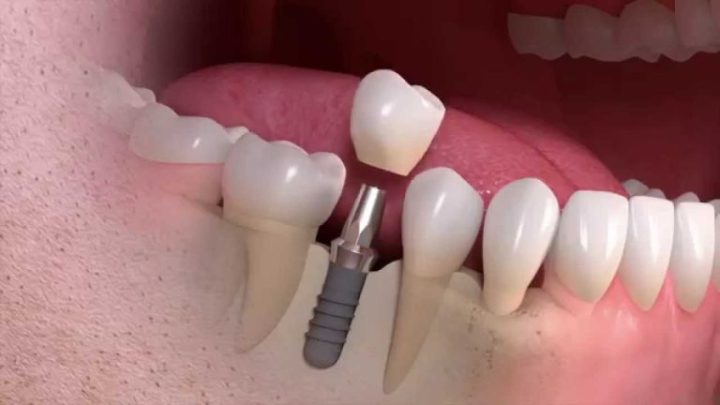

ایمپلنت‌ دندان فرآیندی پیچیده و چند مرحله‌ای است که توسط دکتر سمیرا حاج حیدری، متخصص و دکتر ایمپلنت‌ دندان، به دقت انجام می‌گیرد. در مرحله نخست، بیمار به یک مشاوره جامع دعوت می‌شود تا نیازها و نگرانی‌های او بررسی شود. پس از تصویربرداری های لازم و ارزیابی وضعیت دهان و دندان، برنامه درمانی مناسب تنظیم می‌شود. در مرحله بعد، عمل جراحی برای قرار دادن ایمپلنت در فک انجام می‌شود. این مرحله به دقت و مهارت بالایی نیاز دارد و دکتر حاج حیدری با استفاده از تکنیک‌های پیشرفته، ایمپلنت را در محل مناسب قرار می‌دهد.

پس از قرارگیری ایمپلنت، دوره‌ای از بهبودی آغاز می‌شود که در خلال آن، استخوان فک به تدریج با ایمپلنت جوش می‌خورد و ثبات لازم فراهم می‌شود. پس از این مرحله، پروتز دندان، که می‌تواند تاج یا سایر انواع دندان‌های مصنوعی باشد، بر روی ایمپلنت نصب می‌شود. در نهایت، دکتر سمیرا حاج حیدری با پیگیری‌های منظم و مشاوره‌های لازم، اطمینان حاصل می‌کند که بیمار از نتیجه نهایی راضی باشد و عملکرد و زیبایی دندان‌ها به بهترین نحو ممکن حفظ شود.